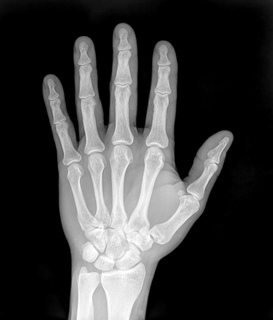

Different frequencies of EM radiation have different degrees of penetration. For example, if we take the human body as the object, visible light is reflected off the surface of the human body, ultra-violet light (from sunlight) damages the skin, but X-rays are able to penetrate the skin and bone and allow for pictures of the inside of the human body to be taken.

X-rays

While X-rays are used significantly in medicine, prolonged exposure to X-rays can lead to cell damage and cancer.

For example, a mammogram is an X-ray of the human breast to detect breast cancer, but if a woman starts having regular mammograms when she is too young, her chances of getting breast cancer increases.